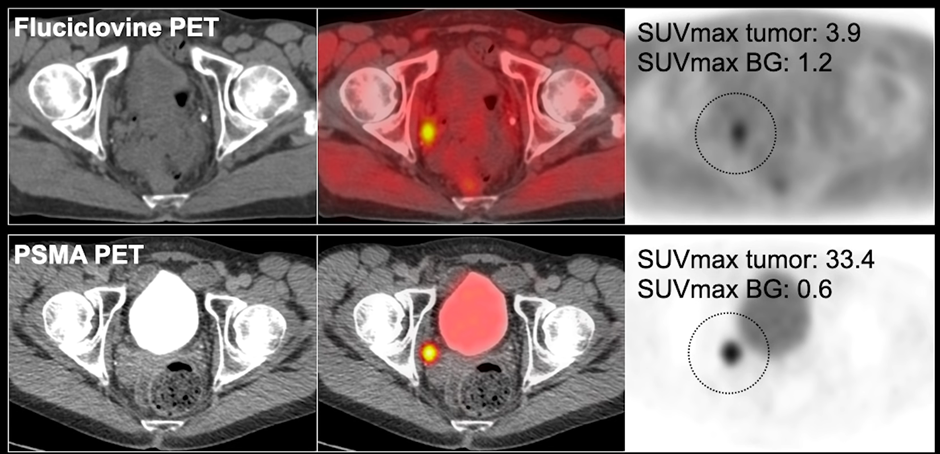

Understanding SUVmax

SUVmax refers to standardized uptake value maximum.

Higher SUV values may indicate:

- Increased tracer uptake

- Greater PSMA expression

- Higher suspicion for active disease

However, SUV interpretation must always be correlated with clinical context.